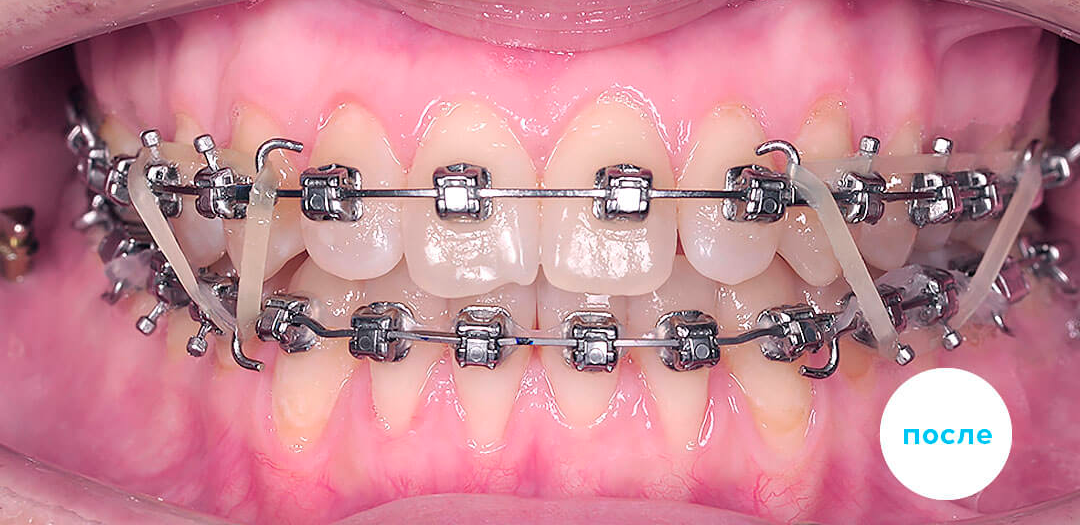

Результаты лечения